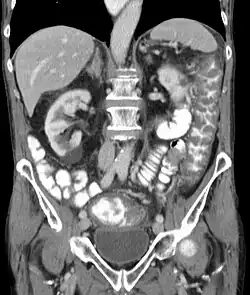

Before the advent of tests to detect C. difficile toxins, the diagnosis most often was made by colonoscopy or sigmoidoscopy. The appearance of "pseudomembranes" on the mucosa of the colon or rectum is highly suggestive, but not diagnostic of the condition.[46] The pseudomembranes are composed of an exudate made of inflammatory debris, white blood cells. Although colonoscopy and sigmoidoscopy are still employed, now stool testing for the presence of C. difficile toxins is frequently the first-line diagnostic approach. Usually, only two toxins are tested for—toxin A and toxin B—but the organism produces several others. This test is not 100% accurate, with a considerable false-negative rate even with repeat testing.[47]